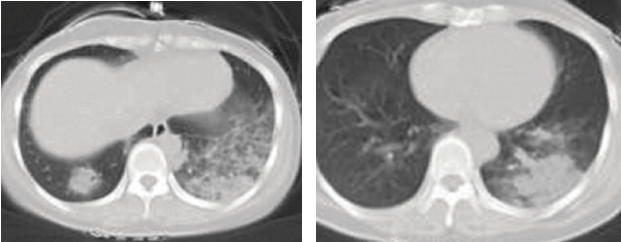

Chest computed tomography (CT) scan showed multiple ground glass appearance in both lungs. She was diagnosed with pneumonia and admitted to hospital. During her stay on a general medical ward, she was prescribed the antibiotic ceftazidime and a patent Chinese herb infusion (Xiyan Ping) for 4 days but showed no significant improvement.

• A third CT scan showed almost complete disappearance of the ground glass appearance. On discharge the patient had complete resolution of symptoms.